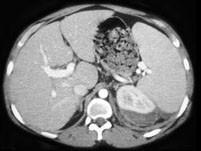

问题 男,35岁,左侧腰部胀痛,有外伤史,请根据所示图像,选择最可能诊断 ( )

选项 A、左肾盂输尿管连接处撕裂 B、左肾动脉撕裂 C、左肾包膜下血肿 D、左肾碎裂 E、左肾挫伤

答案 E